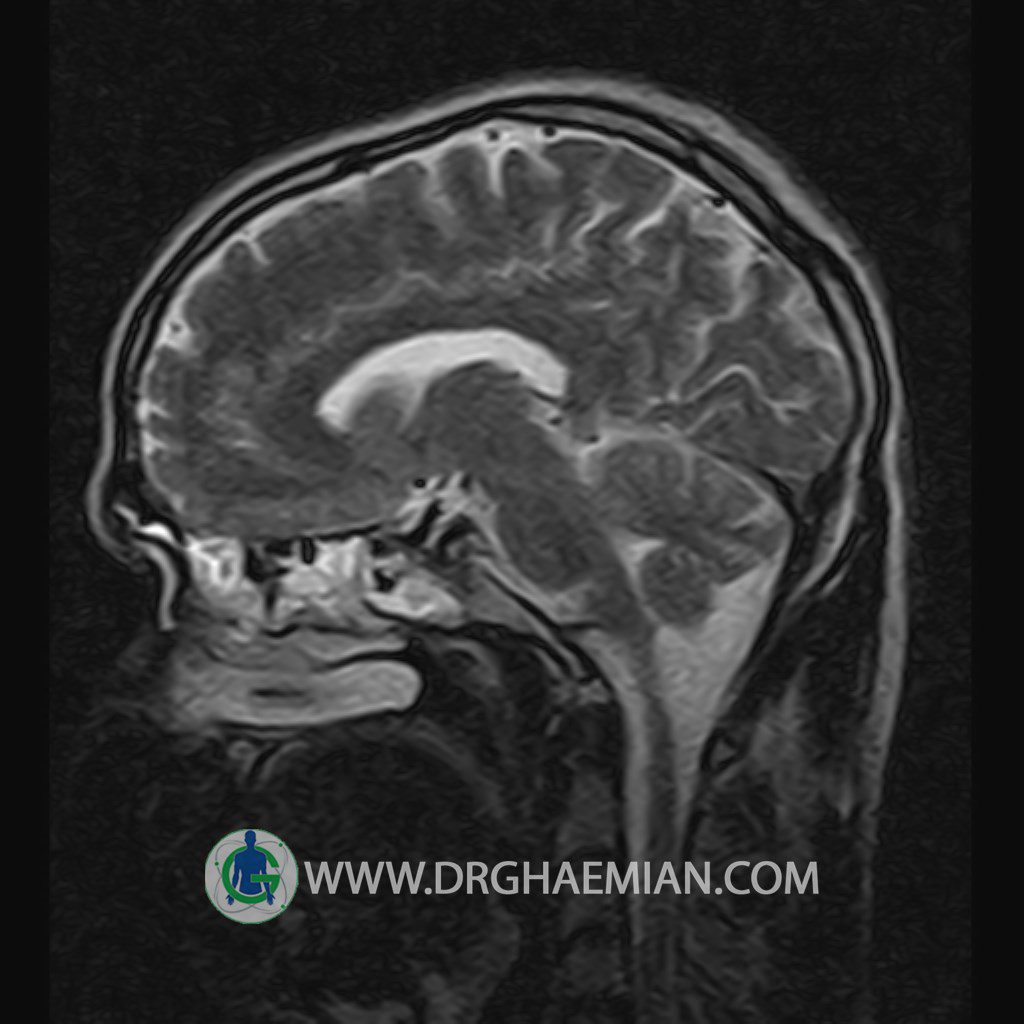

پزشکان اغلب از تصویربرداری ام آر آی برای تشخیص و درمان عارضه های پزشکی که فقط با استفاده از اشعه ایکس یا میدان مغناطیسی و امواج رادیویی قابل مشاهده است، استفاده می کنند. دستگاه ام آر آی تصاویر دقیق از ساختار های داخلی بدن ایجاد می کند. در این کیس یک میکروآدنوم در هیپوفیز بیمار مشاهده می شود.

HYPOPHYSIS MRI

(with and without contrast)

Technique: Axial , coronal T1 , Axial , coronal , sagittal T2 , Axial, coronal T1 post Gd & 64 dynamic thin coronal slices.

The infundibulum is centered and of normal size .

The optic chiasm and suprasellar spaces appear normal .

The cavernous sinus and imaged portions of the internal carotid artery and carotid siphon are unremarkable .

Evaluable portions of the neurocranium show no abnormalities .

The sphenoid sinus is clear and pneumatized .

Imaging of the hypothalamus after contrast medium administration was normal.

– Small hypoenhancing mass lesion ( 3 x 4 mm ) in posterior of pituitary stalk suggestive for micro adenoma

– Mucosal thickening in ethmoid & maxillary sinuses

is seen